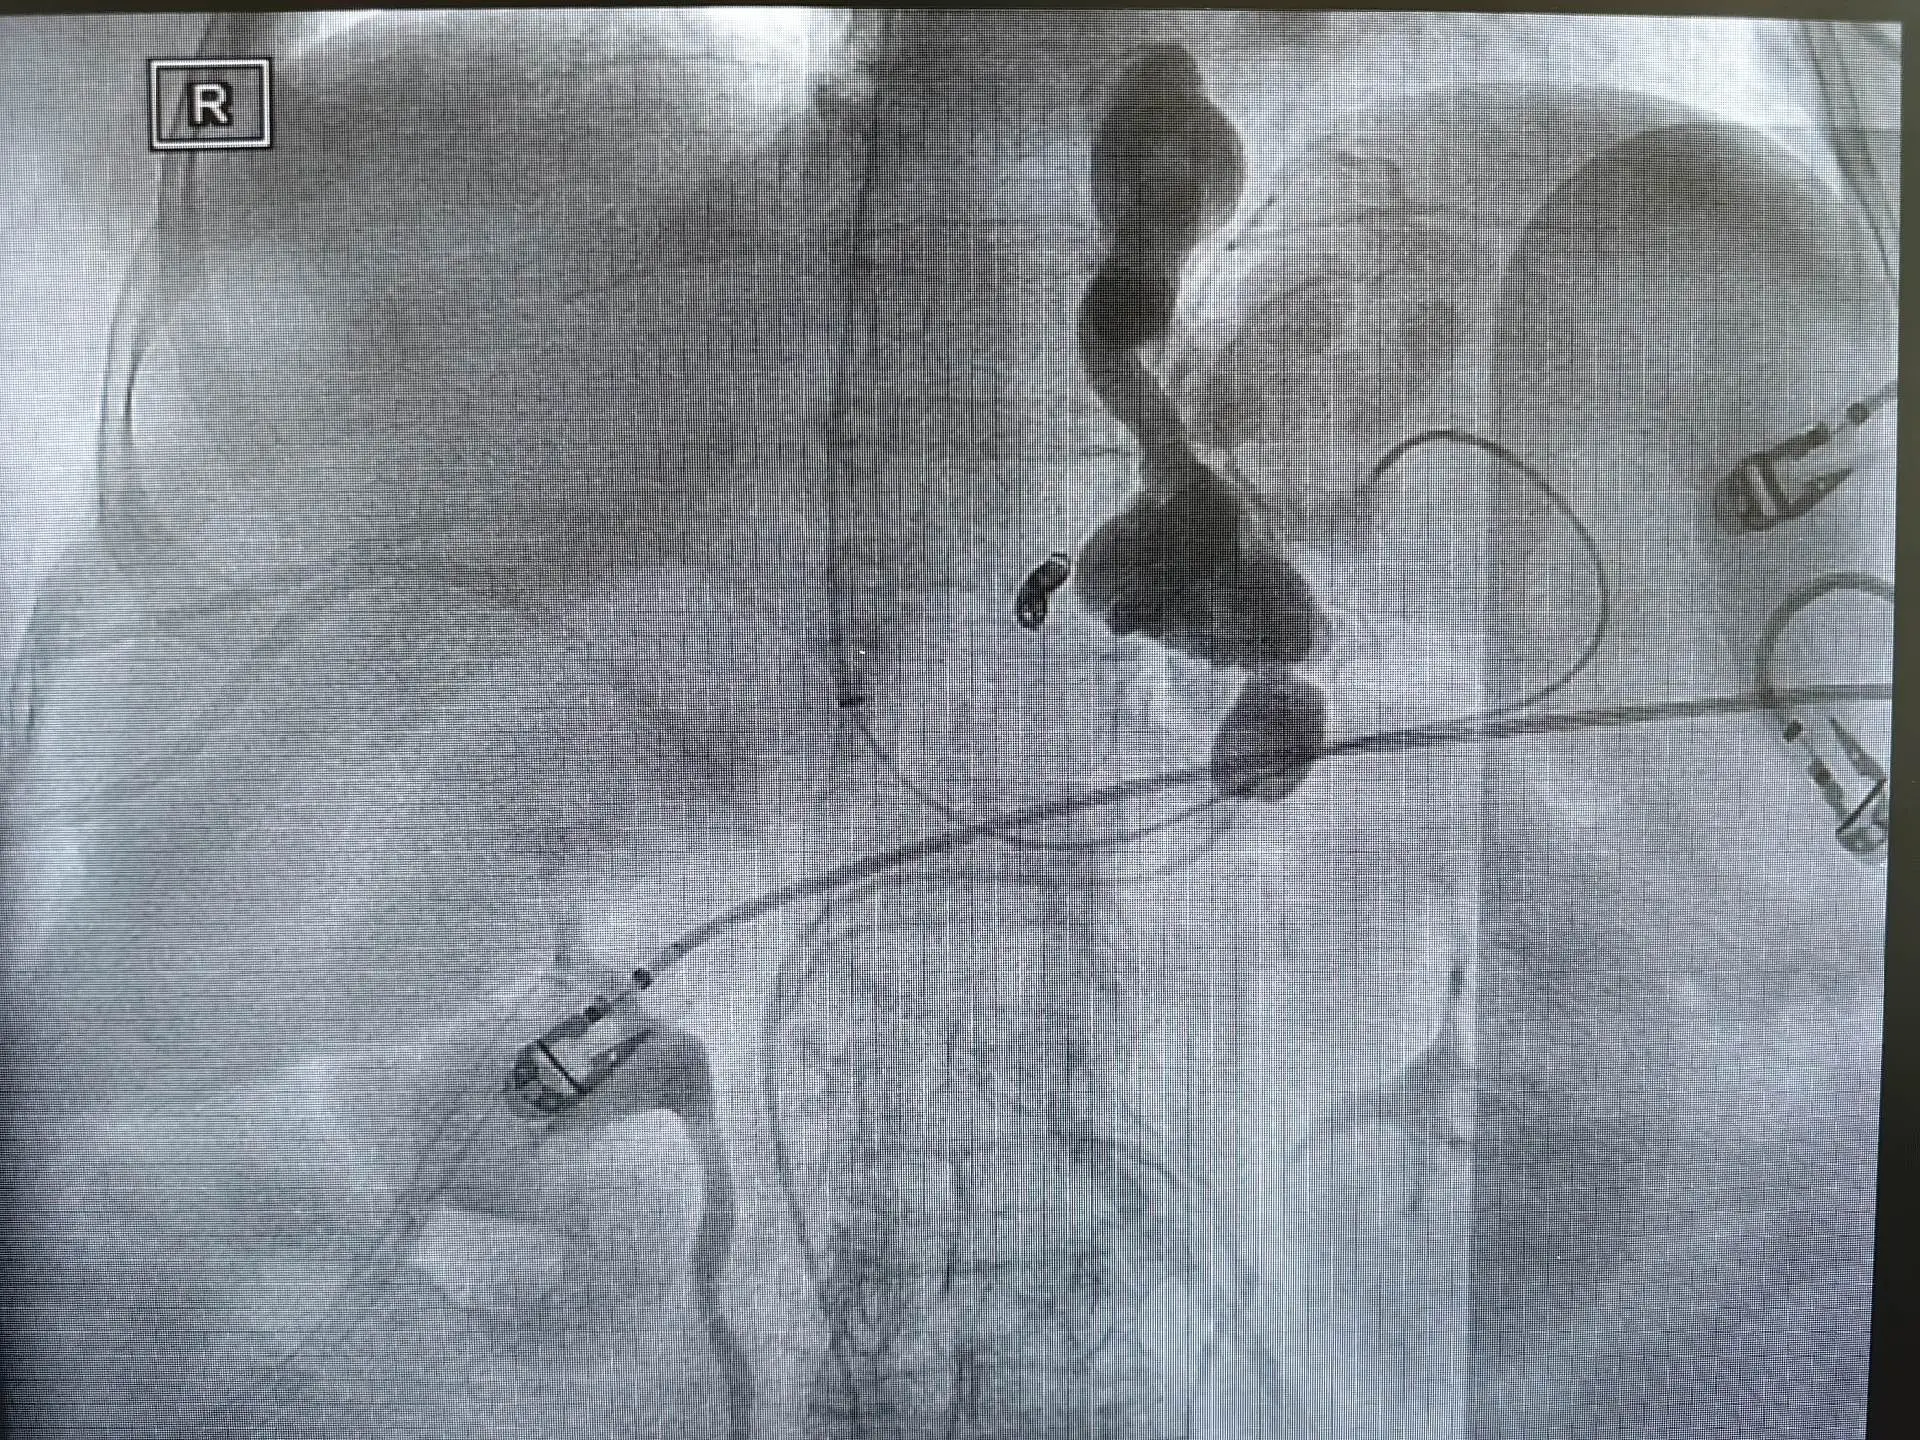

TIPS联合BRTO治疗合并脾胃肾分流的胃底静脉曲张破裂出血患者,大禹治水:疏堵结合